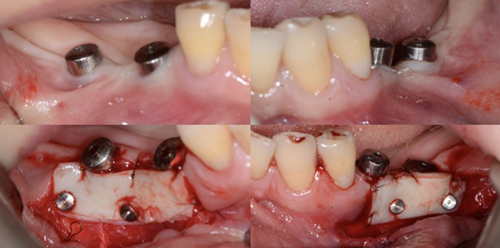

下面是上皮-結(jié)締組織聯(lián)合strip技術(shù)

如下圖:

可見右上前牙植體頰側(cè)無附著齦

為了減少取瓣大小,從上腭取厚一點(diǎn)的齦瓣,然后用刀片平行于表皮表面將齦瓣片切成兩個(gè)厚度一致的齦瓣,然后進(jìn)行移植,這樣切成的兩個(gè)齦瓣一個(gè)有表皮,一個(gè)沒有表皮是單純的結(jié)締組織。如此的片切可以使齦瓣變成雙倍的大小使用,減少了供區(qū)的取瓣面積。